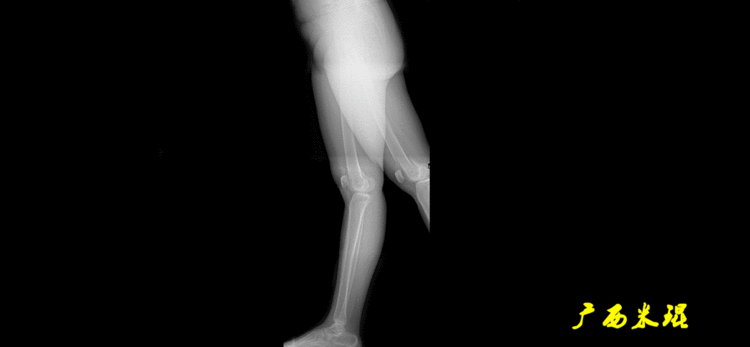

下肢力线及相关角度测量的前提是必须拍摄标准的站立位也就是负重位的下肢全长片。目前这样的照片都是放射科的技师在电脑上拼接出来的,大部分医院的DR都能够做到这一点。

患者直立于摄影架上,后背贴近摄影架,双手自然下垂,膝关节尽量伸直,足部与双肩同宽,要求投照时双髌骨朝正前方,通常患者双足尖应平行向前即可。

提醒一下大家,拍摄过程中应避免下肢的外旋和内旋。如果有一侧肢体短缩时,投照应当用脚垫垫高短缩肢体,使骨盆保持水平,这样下肢短缩测量才精确。如果有肢体旋转畸形时,还是以髌骨朝前为标准,虽然此时双足可能不能保持平行。

下肢全长片的基本要求

无论如何,拍摄出来的下肢全长片必须包含髋关节中心、膝关节中心及踝关节中心,否则对临床是无用的。有了一张下肢的全长照片,我们需要确定下肢关节的中心点,通过中心点画出下肢的各种轴线,然后利用轴线与关节线的相交得出各种所需要的角度。